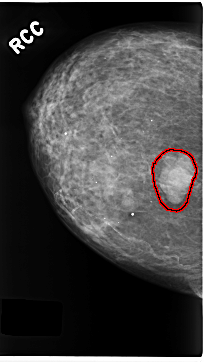

C_0184_1.RIGHT_CC

RIGHT_CC LINES 4704 PIXELS_PER_LINE 2640 BITS_PER_PIXEL 12 RESOLUTION 50 OVERLAY

FILE: C_0184_1.RIGHT_CC.OVERLAY

TOTAL_ABNORMALITIES 1

ABNORMALITY 1

LESION_TYPE MASS SHAPE LOBULATED MARGINS MICROLOBULATED

ASSESSMENT 5

SUBTLETY 5

PATHOLOGY MALIGNANT

TOTAL_OUTLINES 1

BOUNDARY